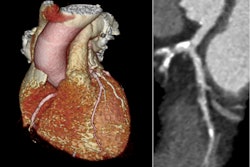

Coronary artery disease (CAD) continues to be the leading cause of death among women in the U.S. and throughout most of the world, the researchers noted. Coronary risk stratification models are important tools for identifying which patients are most likely to experience major adverse cardiovascular events, such as heart attack, stroke, or even death.

All patients underwent gated SPECT myocardial perfusion imaging, an imaging procedure that measures left ventricular function and myocardial perfusion at the same time. The average follow-up time was approximately four years (the maximum was 10 years) and all follow-ups occurred in the hospital as a result of a major adverse cardiovascular event.